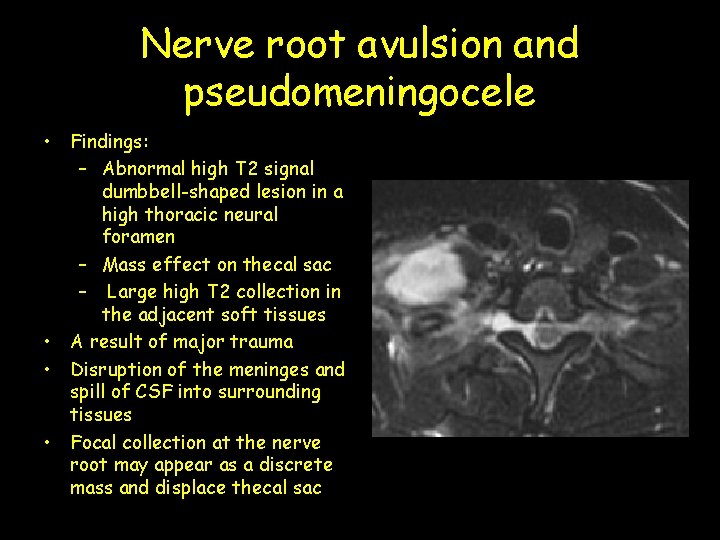

Nerve root avulsion and pseudomeningocele • Findings: – Abnormal high T 2 signal dumbbell-shaped lesion in a high thoracic neural foramen – Mass effect on thecal sac – Large high T 2 collection in the adjacent soft tissues • A result of major trauma • Disruption of the meninges and spill of CSF into surrounding tissues • Focal collection at the nerve root may appear as a discrete mass and displace thecal sac